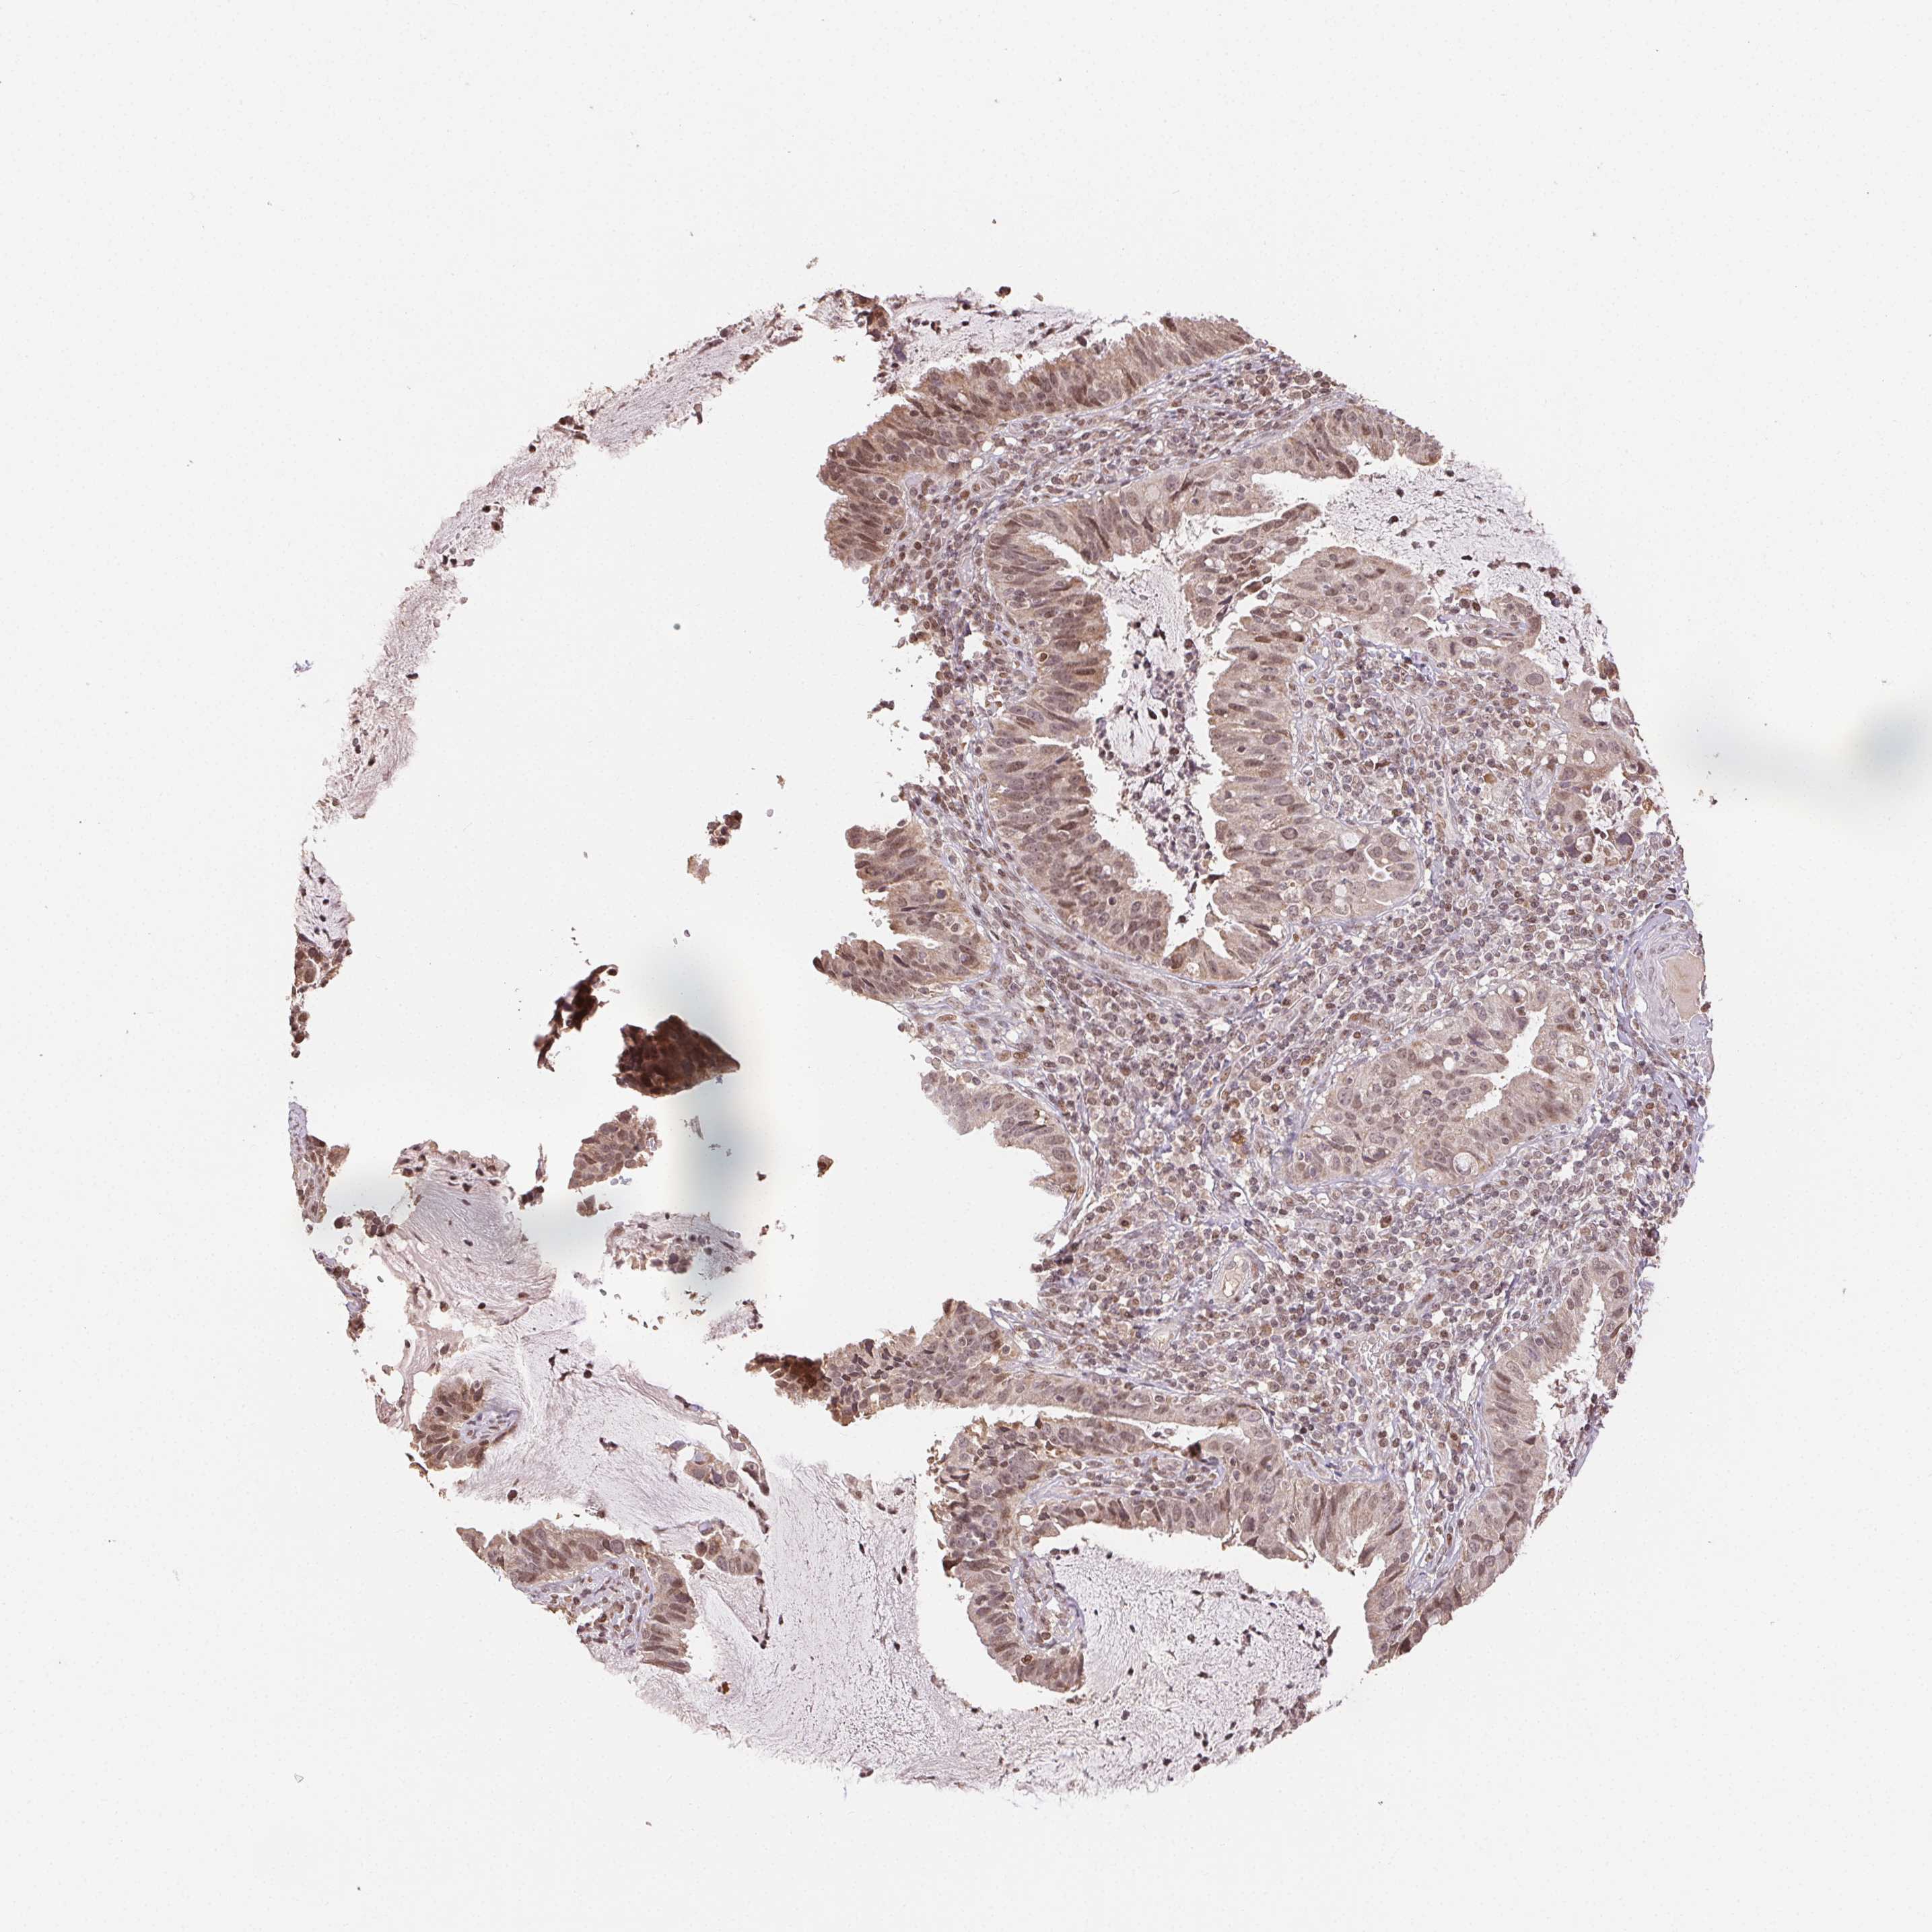

CERVICAL CANCER - Protein expressioni

A mouse-over function shows sample information and annotation data. Click on an image to view it in a full screen mode. Samples can be filtered based on level of antibody staining by selecting one or several of the following categories: high, medium, low and not detected. The assay and annotation is described here.

Note that samples used for immunohistochemistry by the Human Protein Atlas do not correspond to samples in the TCGA dataset.

Antibody stainingi

Antibody staining in the annotated cell types in the current human tissue is reported as not detected, low, medium, or high, based on conventional immunohistochemistry profiling in selected tissues. This score is based on the combination of the staining intensity and fraction of stained cells.

Each image is clickable and will lead to virtual microscopy that enables deeper exploration of all samples and also displays staining intensity scores, fraction scores and subcellular localization as well as patient and tissue information for each sample.

Antibody HPA063708

Antibody HPA064435

Antibody CAB010297

Adenocarcinoma, NOS